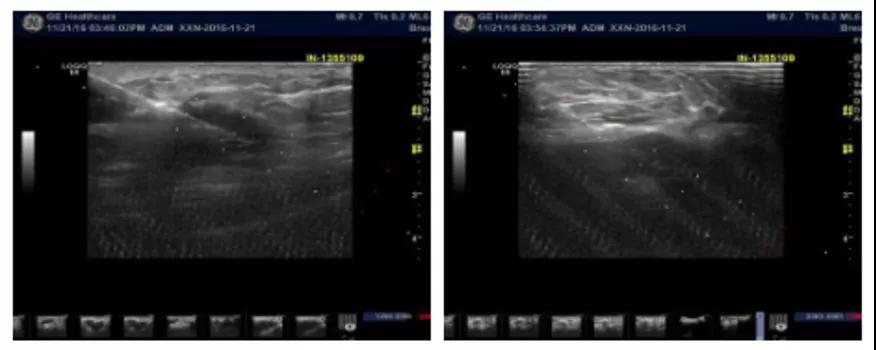

2018-3-5复查B超示:右卵巢内可见约1.6cm×1.5cm无回声区,内可见大小约3.0cm×2.3cm低回声团,子宫左后方可见约6.3cmx3.9cm不均质回声团,边界清,形态欠规则,可见血流信号。